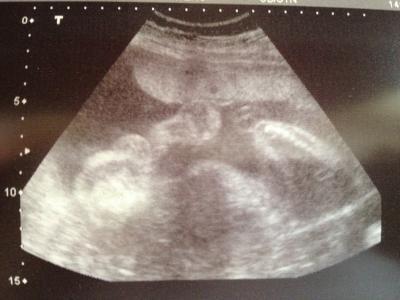

Hey, also unseren Zwerg gehts gut, liegt in SL, Bip 76, KU 259, AU 221, FE 47 (das irritiert mich jetzt weil das letste mal war Fe 49...) u wiegt ca. 950 gr... Was haltet ihr davon, bin heute bei 26+4! Und traraaaaa es wird eindeutig ein Junge, Beweisfoto häng ich euch mal dran :-)! Bin sooo happy dass alles in ordnung ist u wir jetzt endlich auf Namenssuche gehen können...! Lg u einen schönen Tag noch

Bild zu Fa Bericht + Outing - Forum für Mai - Mamis